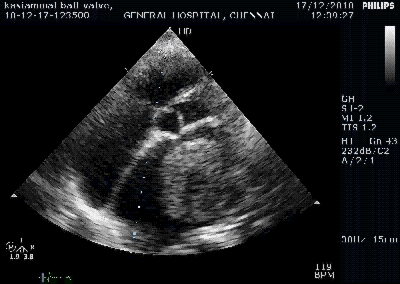

Right from the days we entered medical schools, severe mitral stenosis was defined by less than 1 cm² MVO by echocardiography. It has been sacredly followed in most countries where RHD is prevalent. But, as western data (often derived with eastern patients) redefined the cut off for severe MS to 1.5 cm² in recent years ,.Many of us are amused, rather confused.

1.When there is discrepancy in MVO always go with planimetry. If calcium is there MVO can be problematic; one may add a color flow in short axis to define exact flow borders in mid diastole.